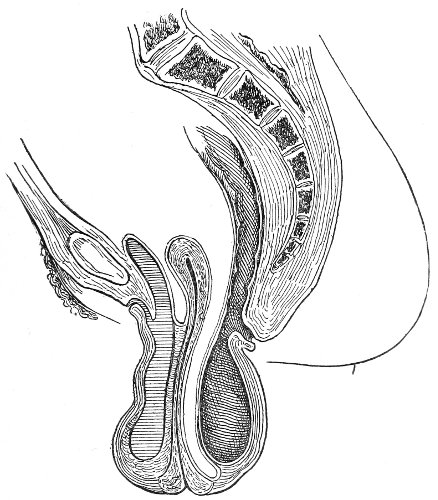

An accurate knowledge of the anatomy and mechanism of the female perineum is essential to an understanding of the nature and treatment of injuries to this structure. The anatomical structures lying between the anus behind and the symphysis pubis in front are those that most directly interest the gynecologist. Proceeding from 57 below upward, we find the following structures lying in superimposed planes: the skin, the superficial fascia, the deep layer of the superficial fascia, the transversus perinæi and the sphincter vaginæ muscles, the anterior layer of the triangular ligament, the posterior layer of the triangular ligament, the levator ani muscle (Fig. 19).

The vagina passes through these structures. They surround and support the ostium vaginæ as the fascia and muscles surround and support the opening of the rectum or the anus. The muscles and fasciæ are attached in the median line between the anus and the vagina, and therefore this part of the body, which is called the perineum, is supported or maintained in its 58 proper position by these various structures. The transversus perinæi arises from the ramus of the ischium and is inserted in the perineum. The bulbo-cavernosus, or sphincter vaginæ, arises in the perineum and is inserted in and about the clitoris. The inner fibers of the levator ani arise from the symphysis pubis and are inserted in the perineum and the lower part of the vagina (Fig. 20). When these muscles contract, their action, therefore, is to draw the perineum upward and forward. At the same time the anus is drawn upward and forward, and so also is the posterior margin of the ostium vaginæ and the lower portion of the posterior vaginal wall.

Fig. 20.—Dissection of female perineum, showing the deeper structures after removal of the levator and sphincter ani muscles.

The vagina has no circular sphincter like the anus, but 59 the vaginal month is kept closed by the action of the transversus perinæi, sphincter vaginæ, and levator ani muscles, which draw the perineum forward, and thus keep the posterior vaginal wall in apposition with the anterior wall.

This sling of muscles and fascia, which surrounds and supports the opening of the vagina, may readily be felt in the nulliparous woman by introducing the finger in the vagina and pressing backward and outward toward the ischio-rectal fossa. We then feel plainly, immediately within the ostium vaginæ, a firm resisting band of tissue, apparently about half an inch broad, embracing the posterior portion of the lower vagina. This band is formed by the inner edges of the various muscles and planes of fascia that have been described.

The vagina extends, as a transverse slit in the pelvic floor, upward and backward, approximately in the direction 60 of a line drawn from the ostium vaginæ to the fifth sacral vertebra. It is approximately parallel with the conjugate of the brim, so that when the woman is erect the long axis of the vagina is inclined at an angle of 60° to the horizon. The vagina is not a vertical open tube: it is a slit in the pelvic floor, in health always closed by the accurate apposition of the anterior and posterior walls (Fig. 21). The anterior vaginal wall is about 2½ inches long in a vertical mesial line. The posterior vaginal wall is about 3½ inches long. The vaginal walls are triangular in shape, being broader above than below. The shape of the normal vagina at the pelvic outlet is shown by Fig. 23. The section here shows the vaginal 61 slit of the shape of the letter H. The portions of the slit extending backward and somewhat outward are called the vaginal sulci or furrows. They are directions of diminished resistance in which tears are liable to occur.